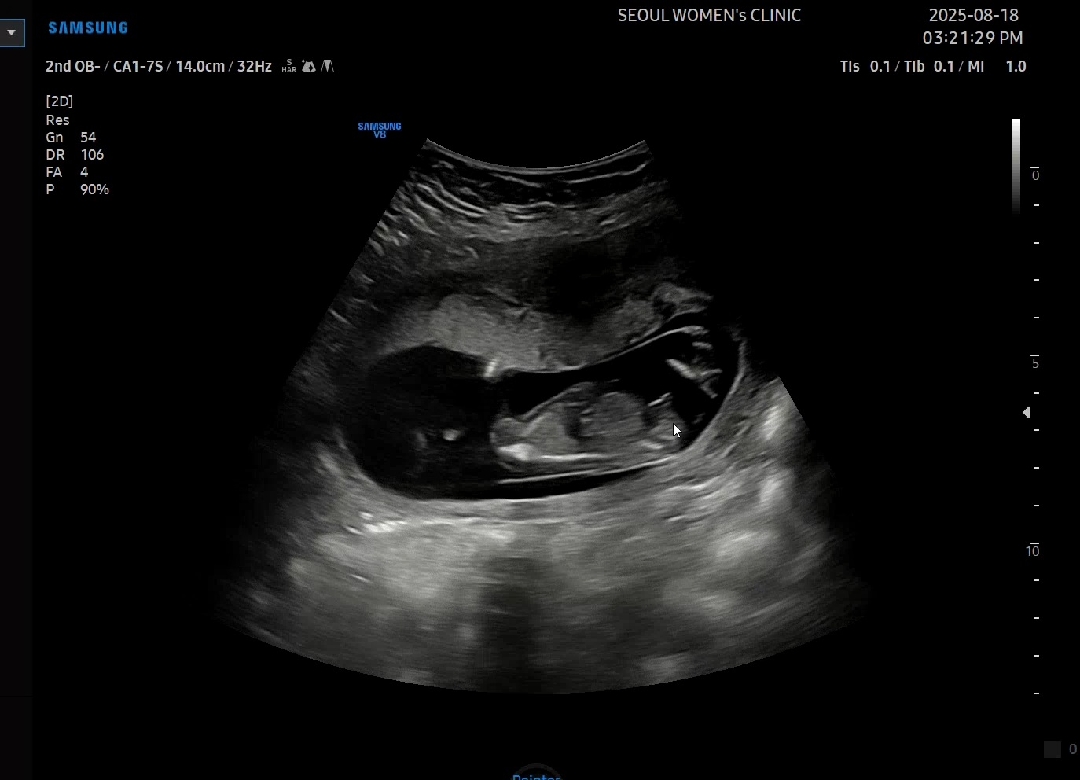

초음파고수님들 각도법 성별문의 13주차🩷

13주차3일 입니다 선생님은 아직 애매하다고 하시네요 아들일까요 딸일까요?

제가 15주4일짼데 저정도묜 아들이에요 ㅋㅋ 저희애기도 아들이라서요 ㅋㅋㅋㅋ 똑같아여

고추 올라간 각도가 아들일 확률이 높네요